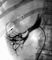

При общей ангиопульмонографии рентгеноконтрастный препарат вводят (чаще через катетер) в верхнюю полую вену, правые предсердие (рис. 3) и желудочек либо через локтевую, подключичную и бедренную вены с той или другой стороны. При селективной ангиопульмонографии под контролем рентгенотелевидения катетер проводят по нижней (через бедренную вену) или верхней (через вены верхней половины тела) полым венам, правому предсердию и желудочку в легочный ствол, куда и вводят рентгеноконтрастный препарат. Катетер может также быть введен в правую или левую легочную артерию (рис. 4) и в сосуды меньшего порядка.